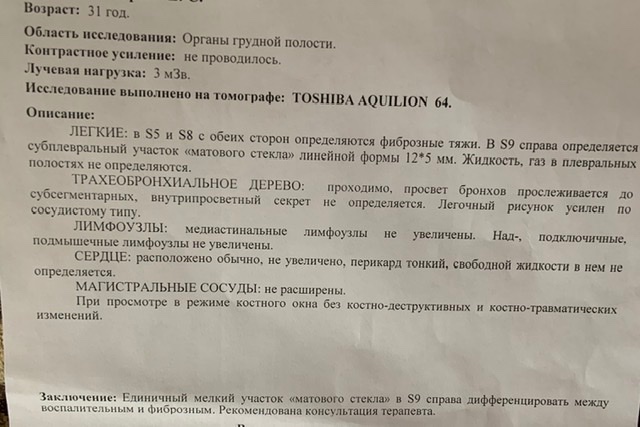

Фотографии и снимки КТ легких без контрастных веществ

Раздел: Визуальный дайджест